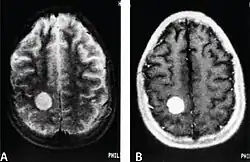

| MRI of a cardiac angiosarcoma that has metastasised to the brain. | |

Primary cardiac angiosarcoma

Primary cardiac angiosarcoma is an angiosarcoma that arises in the heart. Despite being very rare they are the most common malignant primary heart tumor with 10–25%[12][3] of cases being angiosarcomas. Symptoms may include shortness of breath, chest pain (46%[12]), hypotension and syncope. Superior vena cava syndrome is reportedly a complication of cardiac angiosarcoma.[7] Due to the non-specificity of symptoms and rarity of the disease it is often missed by doctors and initial diagnosis may be delayed. A 2012 study reported that 56% of patients presented with pericardial effusion with or without cardiac tamponade.[12] The most common finding on imaging is cardiomegaly. Prognosis is generally very poor with a mean survival rate of three months to four years following diagnosis.[7] Metastasis at time of diagnosis is common.[12]